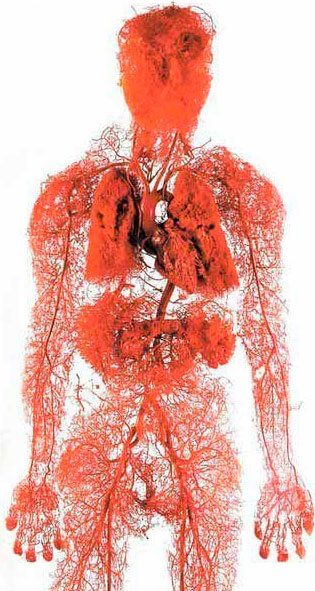

Який найбільший орган у тілі людини? Мало хто знає. Навіть студенти-медики часто помиляються. Найчастіше називають мозок і печінку. Більш освічені кажуть що шкіра. Але насправді найбільший орган це наша судинна система.

2,5 рази

можна оперезати планету судинами 1 людини

Уявіть. Якщо "розплести" всі судини людського тіла і зв'язати їх в одну довгу нитку, то довжина цієї нитки буде приблизно 100 000 кілометрів.

Щоб було зрозуміліше - довжина екватора Землі 40 000 кілометрів.Виходить, що "ниткою" з судин лише 1 людини можна оперезати цілу планету 2,5 рази.

Як вам такий масштаб?

Судини це не просто трубочки, якими тече кров. Це складний і єдиний орган, збій у якому відразу ж вилазить у болячку.